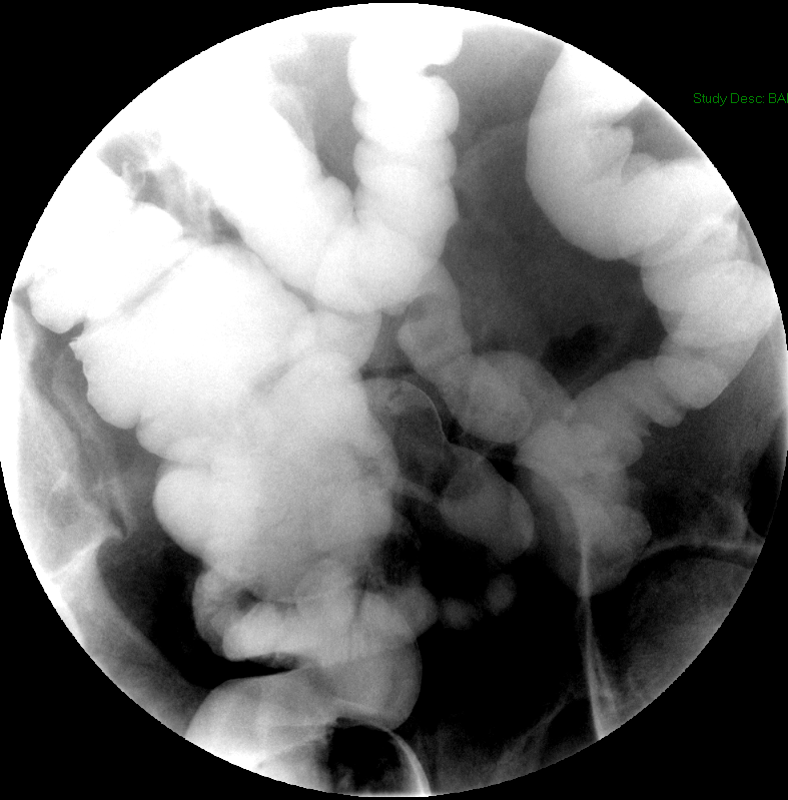

- The technologist will obtain radiographs at 30, 45, and 60 minutes after the initial administration of barium. If the column of contrast material has not reached the large bowel on the 60 minute film, the technologist will obtain images every 30 minutes until contrast can been seen in the cecum

(key image 3)

(key image 4)

(key image 5).